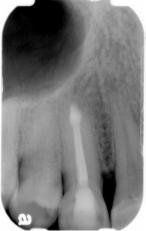

Surgical Endodontics

Success rates for the non-surgical endodontic therapy are in excess of 95% depending on the condition of the involved tooth (cracks, fracture, and/or decays) and surrounding structure like periodontal conditions. Surgical endodontics procedures are usually undertaken when conventional endodontics are failed.

Apicectomy is the surgical removal of the end portion of a root. To achieve this, access to the root apex is gained via a tissue flap and then bone is removed around the root apex. The aim of apicectomy is to eradicate persistent infection in the periapical tissues and to eliminate the 'apical delta' of root canals that cannot be effectively sealed by conventional endodontics and to excise a root apex that cannot be sealed successfully due to anatomical anomalies such as marked root curvature. Root end will be filled with a medicament called MTA, or Mineral Trioxide Aggregate and finished the procedures.